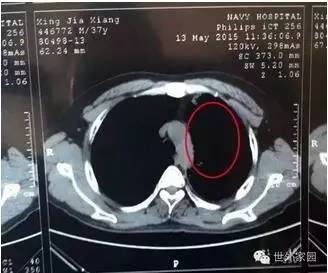

在当地医院的术前常规体检,我被检测出左肺胸腔积液,医院迅速将我从肛肠外科转到呼吸内科。当黑红的血水从胸腔里抽出来的时候,一股不祥的预感让我心惊胆战。度过了忐忑不安漫长的两天等待之后,不出所料,各项检验指标直指最坏结果——肺癌。不甘心,不愿面对现实的我,抱着一丝残存的侥幸希望,在妻子和弟弟的陪伴下踏上北去进京复查的火车。我们来到了海军总医院,找到我的高中好友,海总心胸外科的主治医师。我将生命交给一个信任且值得托付的人。然而残酷无情的现实再一次将我击倒,在意料之中也是意料之外的,经过近十天一系列的检查化验之后,我最后被确诊为肺腺癌四期,西医学上认为的绝症。命运的审判将我牢牢钉在死亡的十字架上。

2014年12月17日CT结果是肿瘤大小7.1*3.5cm

2015年5月13日复查CT肿瘤消失

肿瘤全部消失。(只剩少许胸腔积液,可以随时吸收掉;陈旧性病变是指曾经得肺结核自愈后留下的疤痕。)